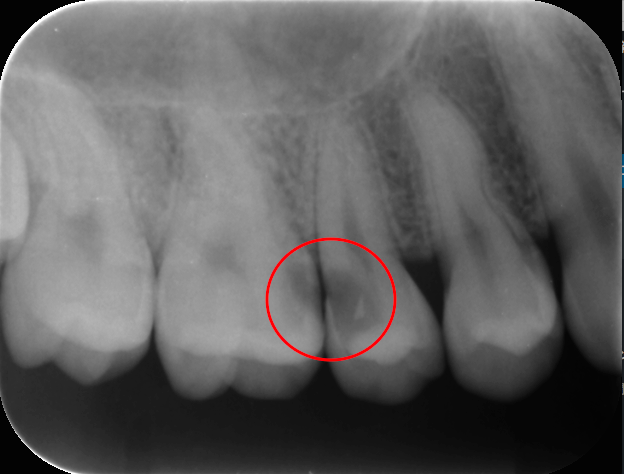

上の画像の赤い丸の部分が虫歯です。この虫歯は口の中を直接見るだけではみつかりません。

この患者さんは痛みはなく、よく食べ物が挟まってしまうと感じていただけでした。